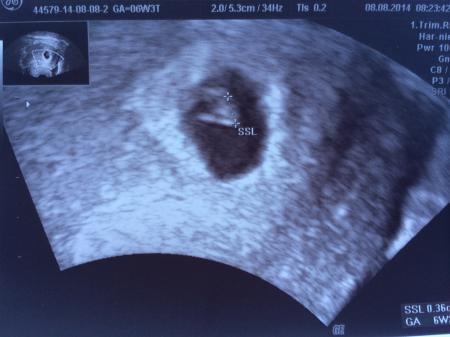

Ich hatte heute auch termin. Herzchen schlägt und krümelchen ist zu sehen. Ich bin überglücklich.

darf natürlich nicht fehlen, aber ich war vorhin noch unterwegs. Bin knapp an der grenze, die FH ist wohl schon etwas größer als mein Krümelchen. Ausgemessen hatte sie heute einmal 6+2 und einmal 6+3, je nachdem wo sie ansetzte...Also ist der ET entweder 31.3. oder 1.4. so hat sies auch in den Mupa geschrieben, und das was nicht stimmt wird dann gestrichen sagte sie. Nächster Termin leider erst am 8.9.

Bild zu